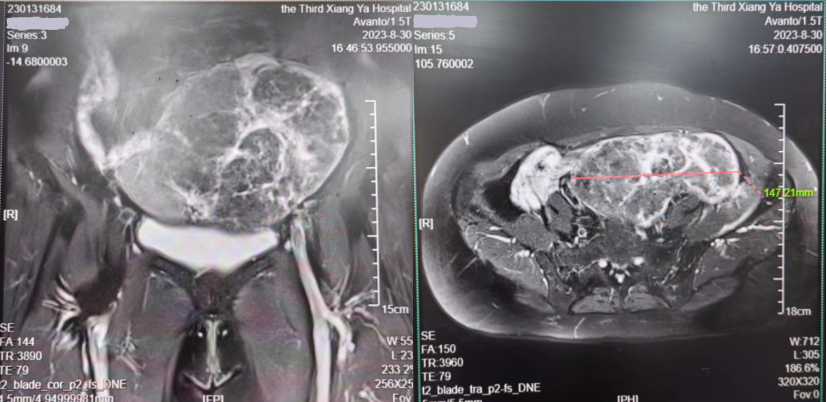

妇科检查示子宫左侧可扪及孕5月大小肿块,完善B超及盆腔MRI均提示巨大阔韧带肌瘤约17cm。MRI图像可见左侧盆腹腔几乎完全被肿块占据,邻近正常组织结构及肠管明显受压推移。为尽快缓解患者症状,决定尽早安排手术。但患者肿块巨大,压迫左侧输尿管及肠管,且患者体型肥胖BMI达28.5,手术难度大,术中出血及损伤风险大。为保障患者尽可能安全顺利地完成手术,肖松舒教授组织医疗小组进行讨论,制定详细的手术计划及讨论围术期处理方案。肖松舒教授仔细研判病情,积极与患者及其家属沟通,最终选择尝试行微创腹腔镜手术,术中见:盆腹腔偏左侧可见一大小约17*15*10cm巨大实性肿块,质硬,探查肿块来自于子宫左侧阔韧带内。平时完成一台普通子宫切除大约30分钟左右,该患者因手术难度较大历经约1小时35分钟,团队顺利完成了腹腔镜下全子宫+双附件切除术。术中出血约100ml。术后6小时患者开始进食进饮,目前恢复良好。